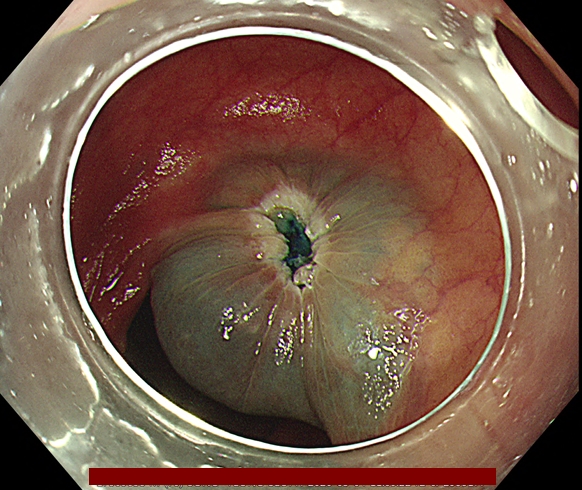

조직 검사 단독으로는 악성 세포의 존재를 배제하거나 악성 세포가 있다는 것을 확증하는데 부적절합니다. 다음 그림과 같이 악성세포가 용종에 존재하지만 조직검사로는 정상 조직을 얻을 수 있기 때문에 용종절제술로 일괄 절제해야 합니다.

오로지 용종을 완전 절제해야만 정확한 조직학적 진단이 가능합니다.

다음은 대장내시경 중 발견된 용종을 일괄 절제한 과정입니다.